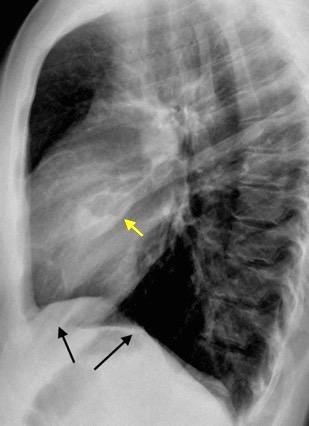

T. mixto de células germinales del testículo

izquierdo Metástasis pulmonares. (flechas verdes). Ganglios paratraqueales. (flechas amarillas). Ganglios retroperitoneales (flechas negras)

Tawfik A et al. Trans-diaphragmatic Pathologies: Anatomical Background and Spread of Disease on cross-sectional Imaging. Current Problems in Diagnostic Radiology. 2021.